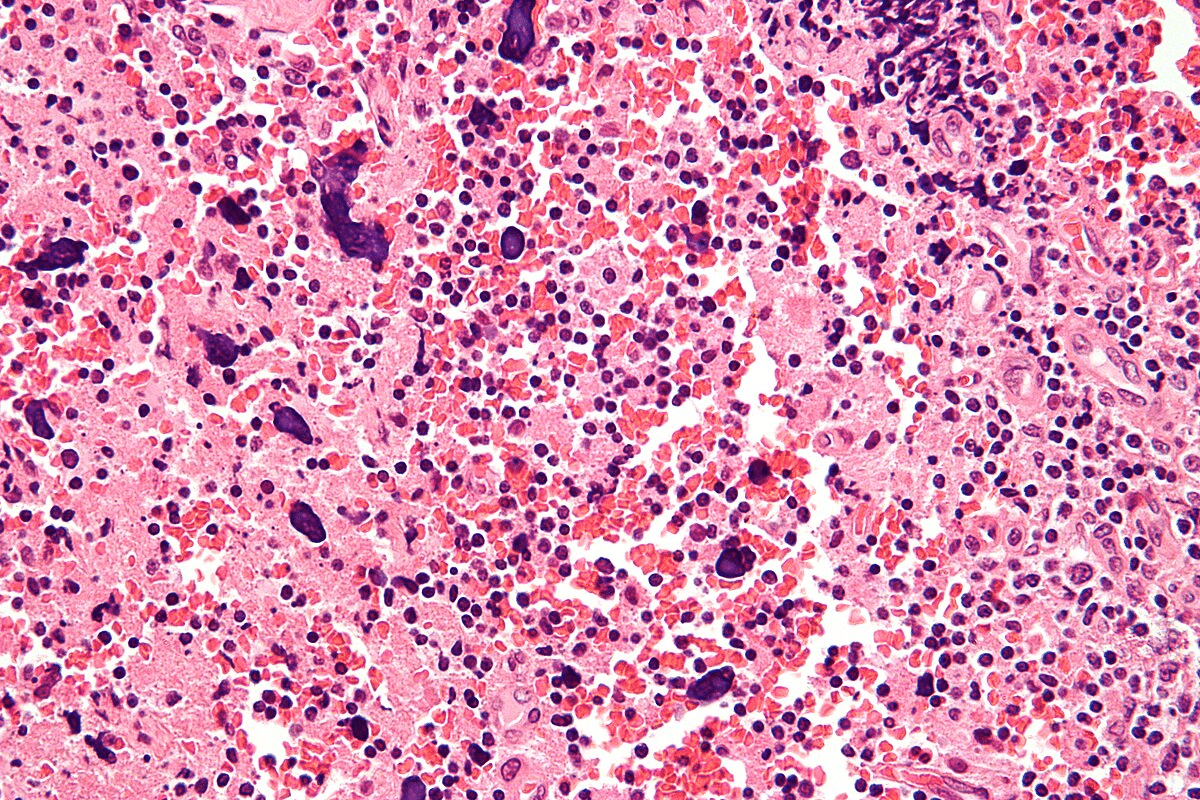

Histopathologic Features

The main signs of LCV include inflammation and damage to the vessel walls. You’ll also see neutrophil fragmentation, red blood cell leakage, and sometimes, immune complexes.

Diagnosing LCV requires a detailed look at skin biopsies or affected tissues. This helps identify the specific vascular changes.

Skin Biopsy and Histopathology

A skin biopsy is a key tool for diagnosing LCV. It shows signs of the condition like leukocytoclasis and inflammation. This helps confirm the diagnosis and gives clues about the cause.

The biopsy findings help doctors understand how severe LCV is and what might have caused it.